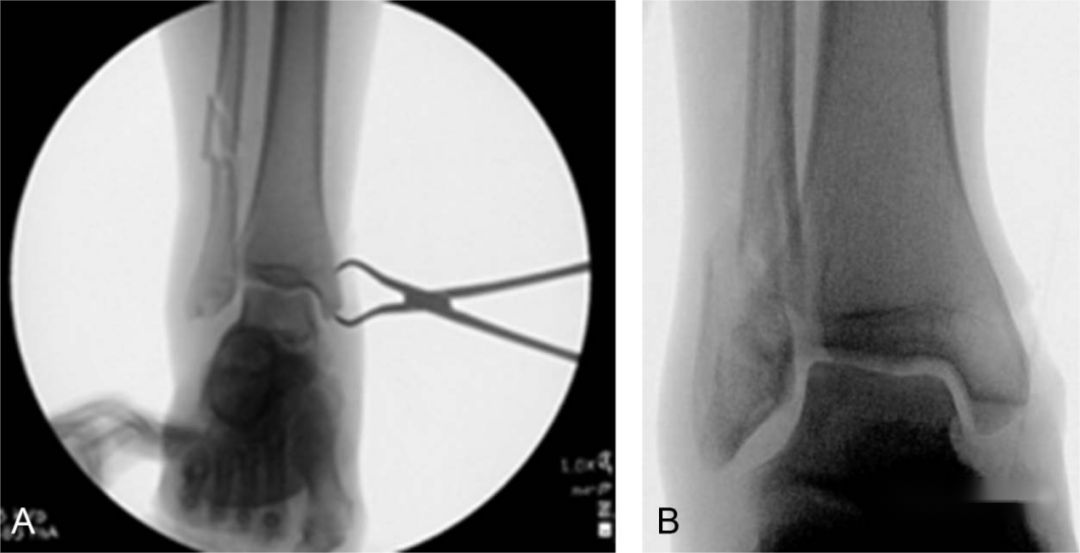

Following the reduction of a lateral malleolus fracture, two 1.6mm non-threaded Kirschner wires are inserted through the distal fragment of the lateral malleolus. They are placed directly to fix the lateral malleolus fragment to the tibia, maintaining the length and rotation of the lateral malleolus and preventing subsequent displacement during further treatment.

During the definitive fixation in the second stage, the Kirschner wires can be threaded out through the holes in the plate. Once the plate is securely fixed, the Kirschner wires are removed, and screws are then inserted through the Kirschner wire holes for additional stabilization.